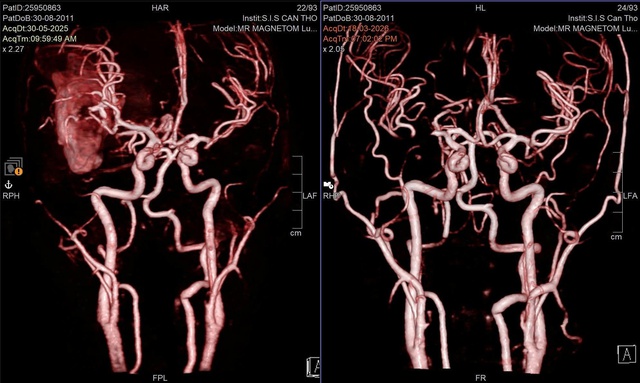

Tại đây, các bác sĩ nhanh chóng xác định bệnh nhi bị xuất huyết não do vỡ dị dạng mạch máu não (AVM) – một bệnh lý bẩm sinh nguy hiểm, thường diễn tiến âm thầm nhưng có thể gây tử vong trong thời gian rất ngắn khi vỡ.

BS.CKI Nguyễn Quang Hưng – Trưởng Đơn vị Phẫu thuật Thần kinh – cho biết, bệnh nhi có dị dạng mạch máu phức tạp kèm khối máu tụ lớn nên ê-kíp đã lựa chọn chiến lược điều trị phối hợp.

"Bệnh nhân được can thiệp nội mạch để giảm lưu lượng dòng chảy, hạn chế chảy máu, sau đó tiến hành phẫu thuật bóc tách và loại bỏ hoàn toàn khối dị dạng" – BS Hưng thông tin.